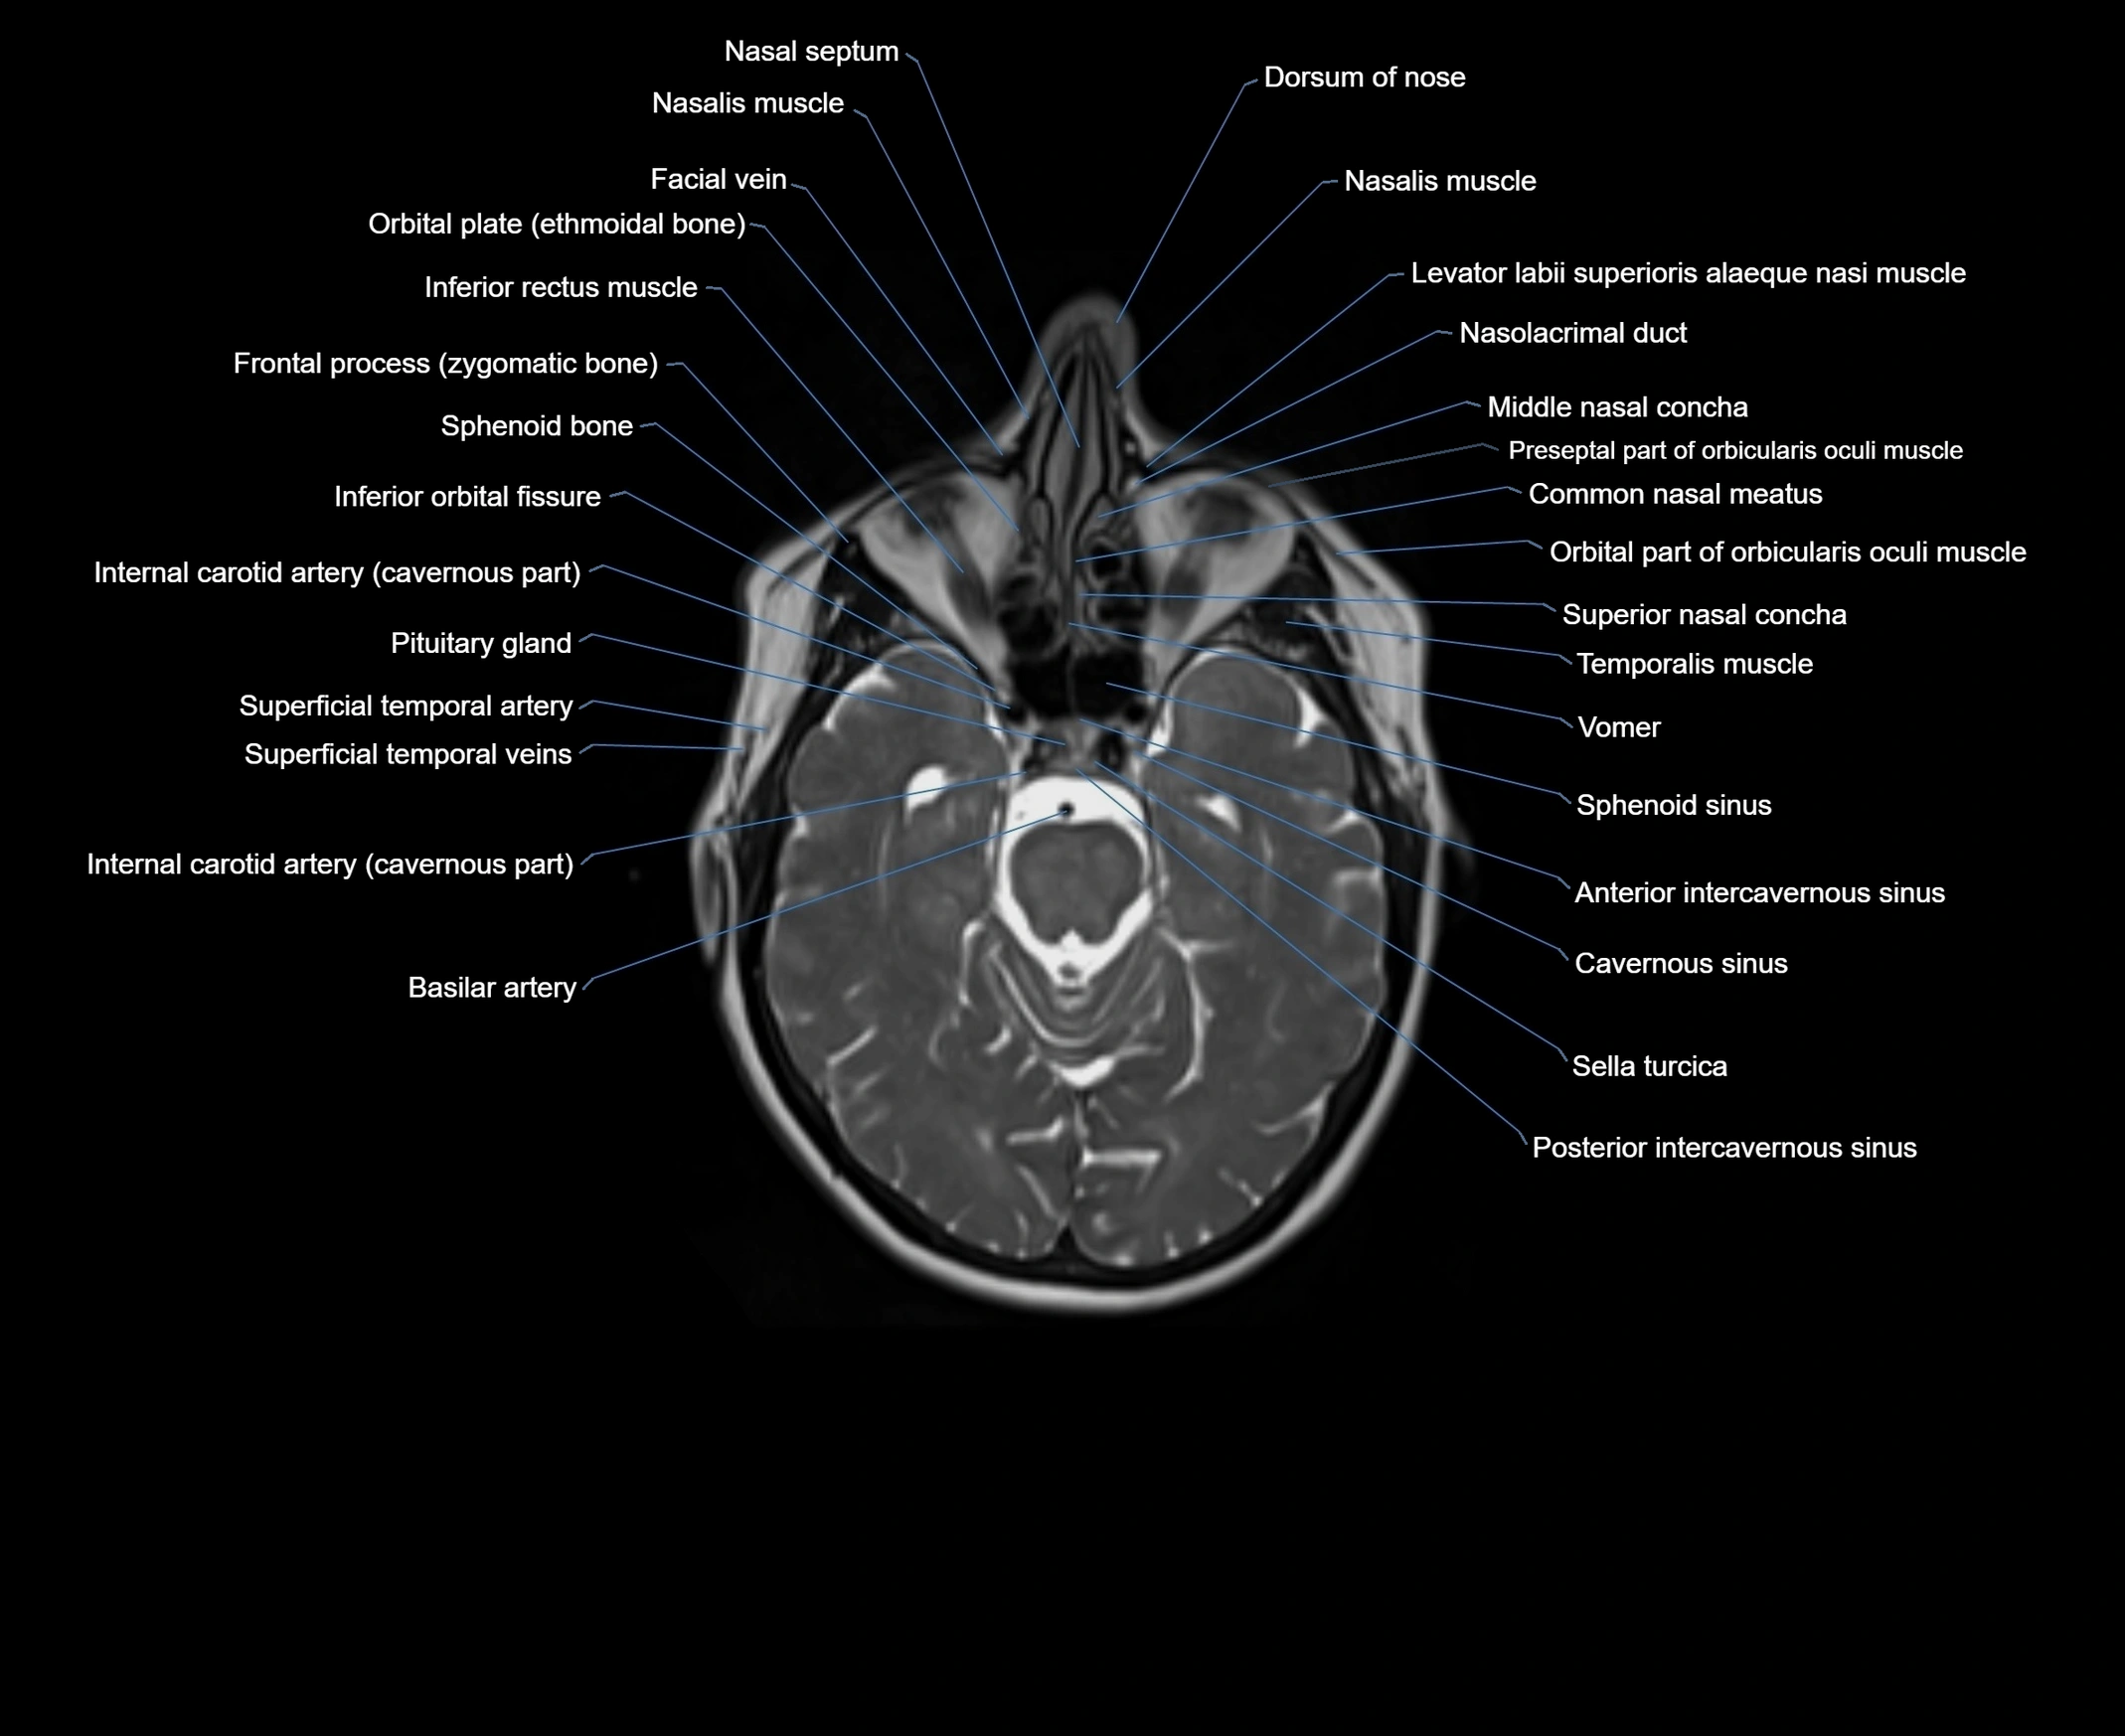

- Common nasal meatus

- Internal carotid artery (cavernous part)

- Middle nasal concha

- Nasofrontal vein

- Sphenoid sinus

- Superficial temporal artery

- Superficial temporal vein

- Superior nasal concha